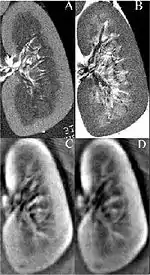

Thermoacoustic imaging was originally proposed by Theodore Bowen in 1981 as a strategy for studying the absorption properties of human tissue using virtually any kind of electromagnetic radiation.[1] But Alexander Graham Bell first reported the physical principle upon which thermoacoustic imaging is based a century earlier.[2] He observed that audible sound could be created by illuminating an intermittent beam of sunlight onto a rubber sheet. Shortly after Bowen's work was published, other researchers proposed methodology for thermoacoustic imaging using microwaves.[3] In 1994 researchers used an infrared laser to produce the first thermoacoustic images of near-infrared optical absorption in a tissue-mimicking phantom, albeit in two dimensions (2D).[4] In 1995 other researchers formulated a general reconstruction algorithm by which 2D thermoacoustic images could be computed from their "projections," i.e. thermoacoustic computed tomography (TCT).[5] By 1998 researchers at Indiana University Medical Center[6] extended TCT to 3D and employed pulsed microwaves to produce the first fully three-dimensional (3D) thermoacoustic images of biologic tissue [an excised lamb kidney (Fig. 1)].[7] The following year they created the first fully 3D thermoacoustic images of cancer in the human breast, again using pulsed microwaves (Fig. 2).[8] Since that time, thermoacoustic imaging has gained widespread popularity in research institutions worldwide.[9][10][11][12][13][14][15] As of 2008, three companies were developing commercial thermoacoustic imaging systems – Seno Medical,[16] Endra, Inc.[17] and OptoSonics, Inc.[18]